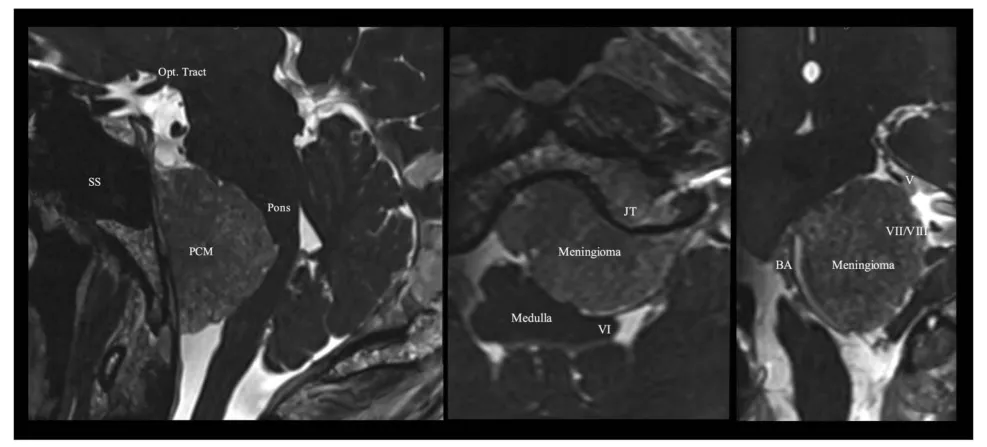

图2. 术前栓塞后,采用稳态构成干涉序列的多平面重建磁共振成像,显示脑膜瘤与神经血管结构的关系。BA,基底动脉;JT,颈静脉结节;Opt. Tract,视束;PCM,岩斜区脑膜瘤;SS,蝶窦;V,第五对颅神经;VI,第六对颅神经;VII/VIII,第七和第八对颅神经。